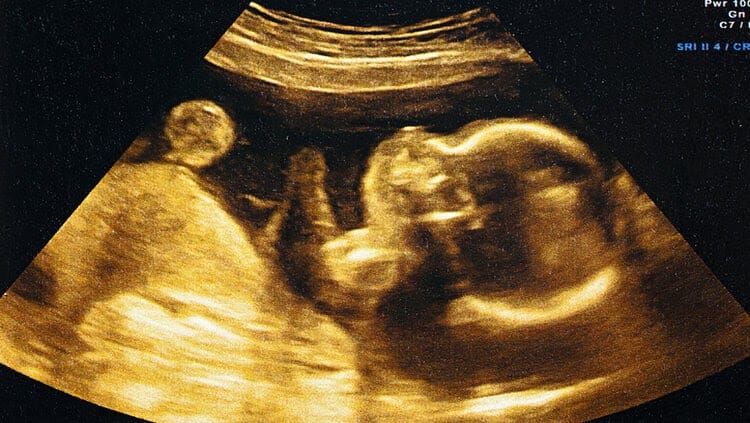

السونار التفصيلي للجنين يتم إجراءه عن طريق جهاز الموجات فوق الصوتية وذلك في الشهر الخامس من الحمل لتوضيح وكشف التشوهات الخلقية وبعض الاضطرابات الوظيفة لأعضاء الجسم لأخذ التدابير التي تعالج أو تخفف من هذه المشاكل ويمكن استخدام تقنية 4D معها أو ال 2D يعني بالنهاية يتم استخدام المسمين لنفس الغرض.

- غالبًا ما يتم إجراء فحص مسح الأعضاء المبكر بين الأسابيع 14 – 17 من الحمل أي خلال الشهر الرابع، ويتيح إجراء الفحص في هذا الوقت المبكر من الحمل إمكانية إجراء المزيد من الفحوص الإضافية والأكثر توسعًا في حال تم تشخيص عيوب خلقية لدى الجنين، أو حتى الإجهاض وإيقاف الحمل إذا استدعى الأمر ذلك.

- أما فحص مسح الأعضاء المتأخر فيتم إجراؤه بالغالب بين الأسابيع 18 – 22 من الحمل. وعلى الرغم أن الجنين الذي يتم فحصه هو ذات الجنين، إلا أن بعض العيوب الخلقية قد يكون من الصعب بل ومن غير الممكن أحيانًا رؤيتها خلال مسح الأعضاء المبكر.